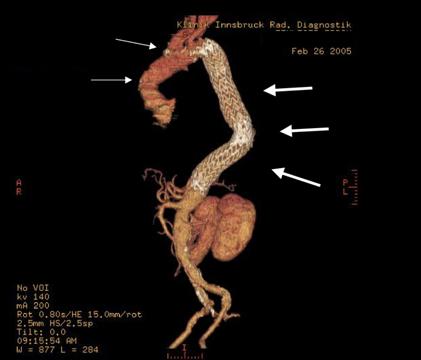

Schließlich sollte der Vollständigkeit halber auch erwähnt werden, dass in den letzten Jahren zunehmend endovaskuläre, interventionelle Verfahren Eingang in die thorakale Aortenchirurgie gefunden haben, d.h. Prothesen können zur Stabilisierung von Aneurysmen (meist) über die Leistengefäße eingebracht werden und im Bereich der (sackartig) erweiterten Hauptschlagader positioniert und expandiert werden. Sie stabilisieren somit die Schwachstelle, exkludieren die sackartige Erweiterung der Schlagader und reduzieren das Rupturrisiko. Dies kann in einigen Fällen dem Patienten eine aufwändige Operation mit Eröffnung des Brustkorbes ersparen (Abb. 3a. und 3b.). Die Entwicklung dieser implantierbaren Prothesen (Stents) läuft derzeit so stürmisch ab, dass noch nicht absehbar ist, welche Bereiche der Aortenchirurgie und in welchem Ausmaß zukünftig interventionelle Verfahren die etablierte herzchirurgische Aortenchirurgie ersetzen werden.

Abb. 3b . Das Aneurysma der Aorta ascendens wurde operativ mittels Protheseninterposition ssaniert, das der Aorta descendens Interventionell durch Applikation zweier Stents (weisses Gitter), die in die Bauchschlagader hineinragen.